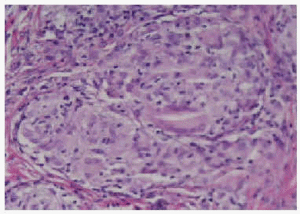

Realizamos biopsia de varias lesiones. El estudio histopatológico mostró, bajo una epidermis normal, la presencia de granulomas que ocupaban prácticamente toda la dermis (fig. 4). Los granulomas estaban constituidos por histiocitos, células gigantes multinucleadas, y no presentaban necrosis (fig. 5). Periféricamente se podía observar en ocasiones una fina corona linfocitaria. Con la técnica de Ziehl-Neelsen no se observaron bacilos ácido-alcohol resistentes. La microscopia de luz polarizada no reveló la presencia de material extraño. La baciloscopia y el cultivo de Lowenstein realizados sobre la muestra de biopsia resultaron negativos.

Fig. 4.--A: granulomas no caseificantes en dermis, con ocasionales células gigantes (hematoxilina-eosina, x40); B: cúmulos de células epitelioides (hematoxilina-eosina, x300).

Fig. 5.--Granuloma no caseificante con infiltrado linfocitario periférico (hematoxilina-eosina x120).